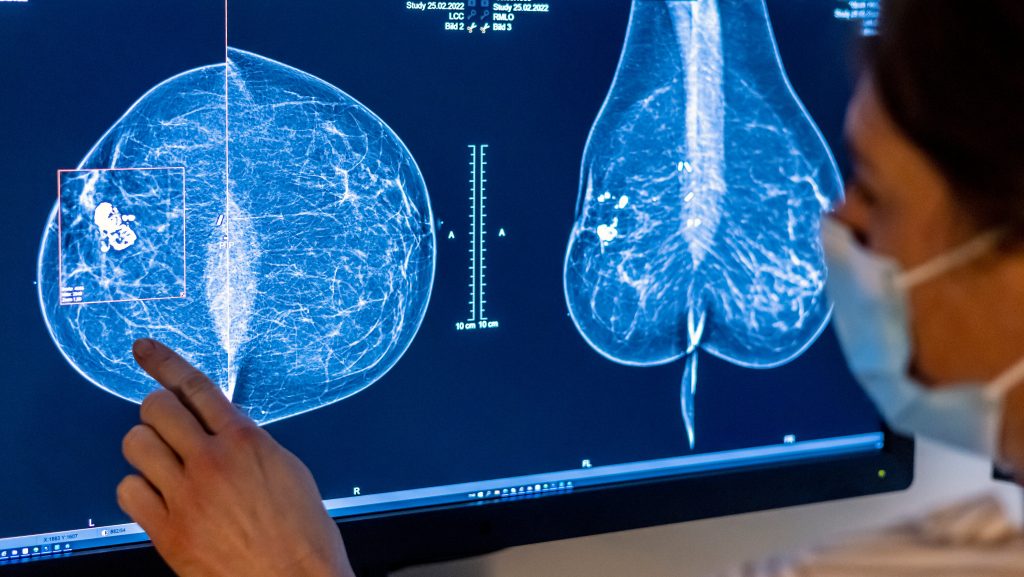

Mammography

Digital mammography is the cornerstone of population-based screening. It uses low-dose X-rays to produce breast images, detecting microcalcifications or masses years before palpability.

- Types: 2D digital; 3D tomosynthesis (DBT) reduces recall rates by 15-20% and improves cancer detection by 20-40%, especially in dense breasts.

- Performance: Sensitivity 85-90% overall; lower (~60%) in dense breasts. Specificity ~90%, leading to false positives requiring follow-up.

Benefits: 20-40% mortality reduction in screened populations. Harms: Radiation exposure (minimal), anxiety from recalls, overdiagnosis of indolent cancers.